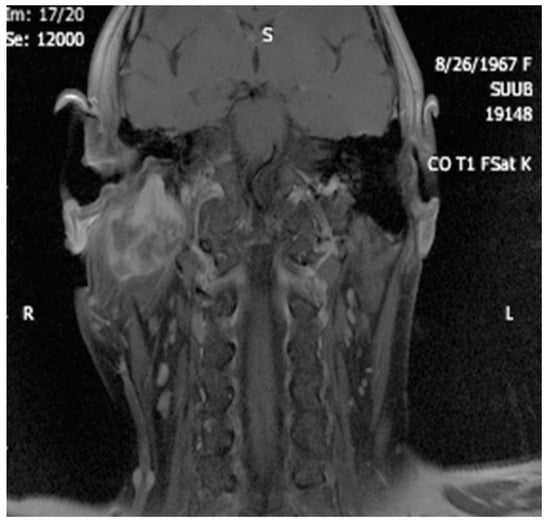

4. Imagery in Extracranial FNSs